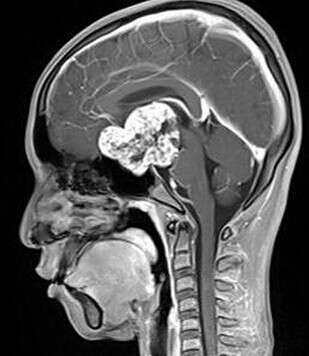

患者:男,15岁,双眼视力下降1年余,近来有嗜睡表现。

【正确答案】A 颅咽管瘤

(1)颅咽管瘤的两个发病高峰年龄分别是4-15岁和35-45岁,其中实性颅咽管瘤多见于成年人,本例为青少年患者,发病年龄无特异性;

(2)对诊断有提示意义的征象是明显强化,内散在微囊状不强化区。